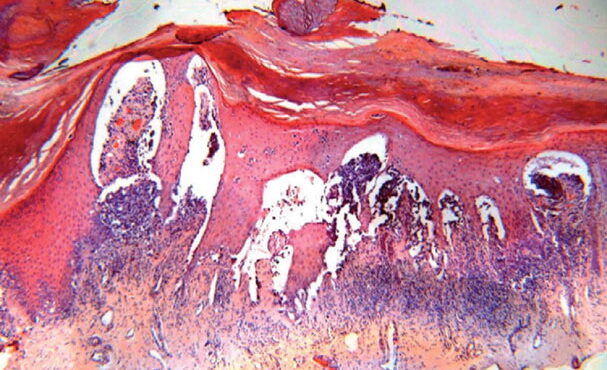

Acquired progressive lymphangioma =الورم الوعائي اللمفاوي المترقي المكتسب